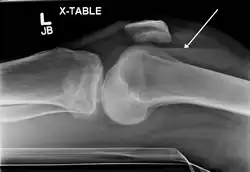

-

Lipohemarthrosis due to a tibial plateau fracture -

Subtle tibial plateau fracture on an AP X ray of the knee -